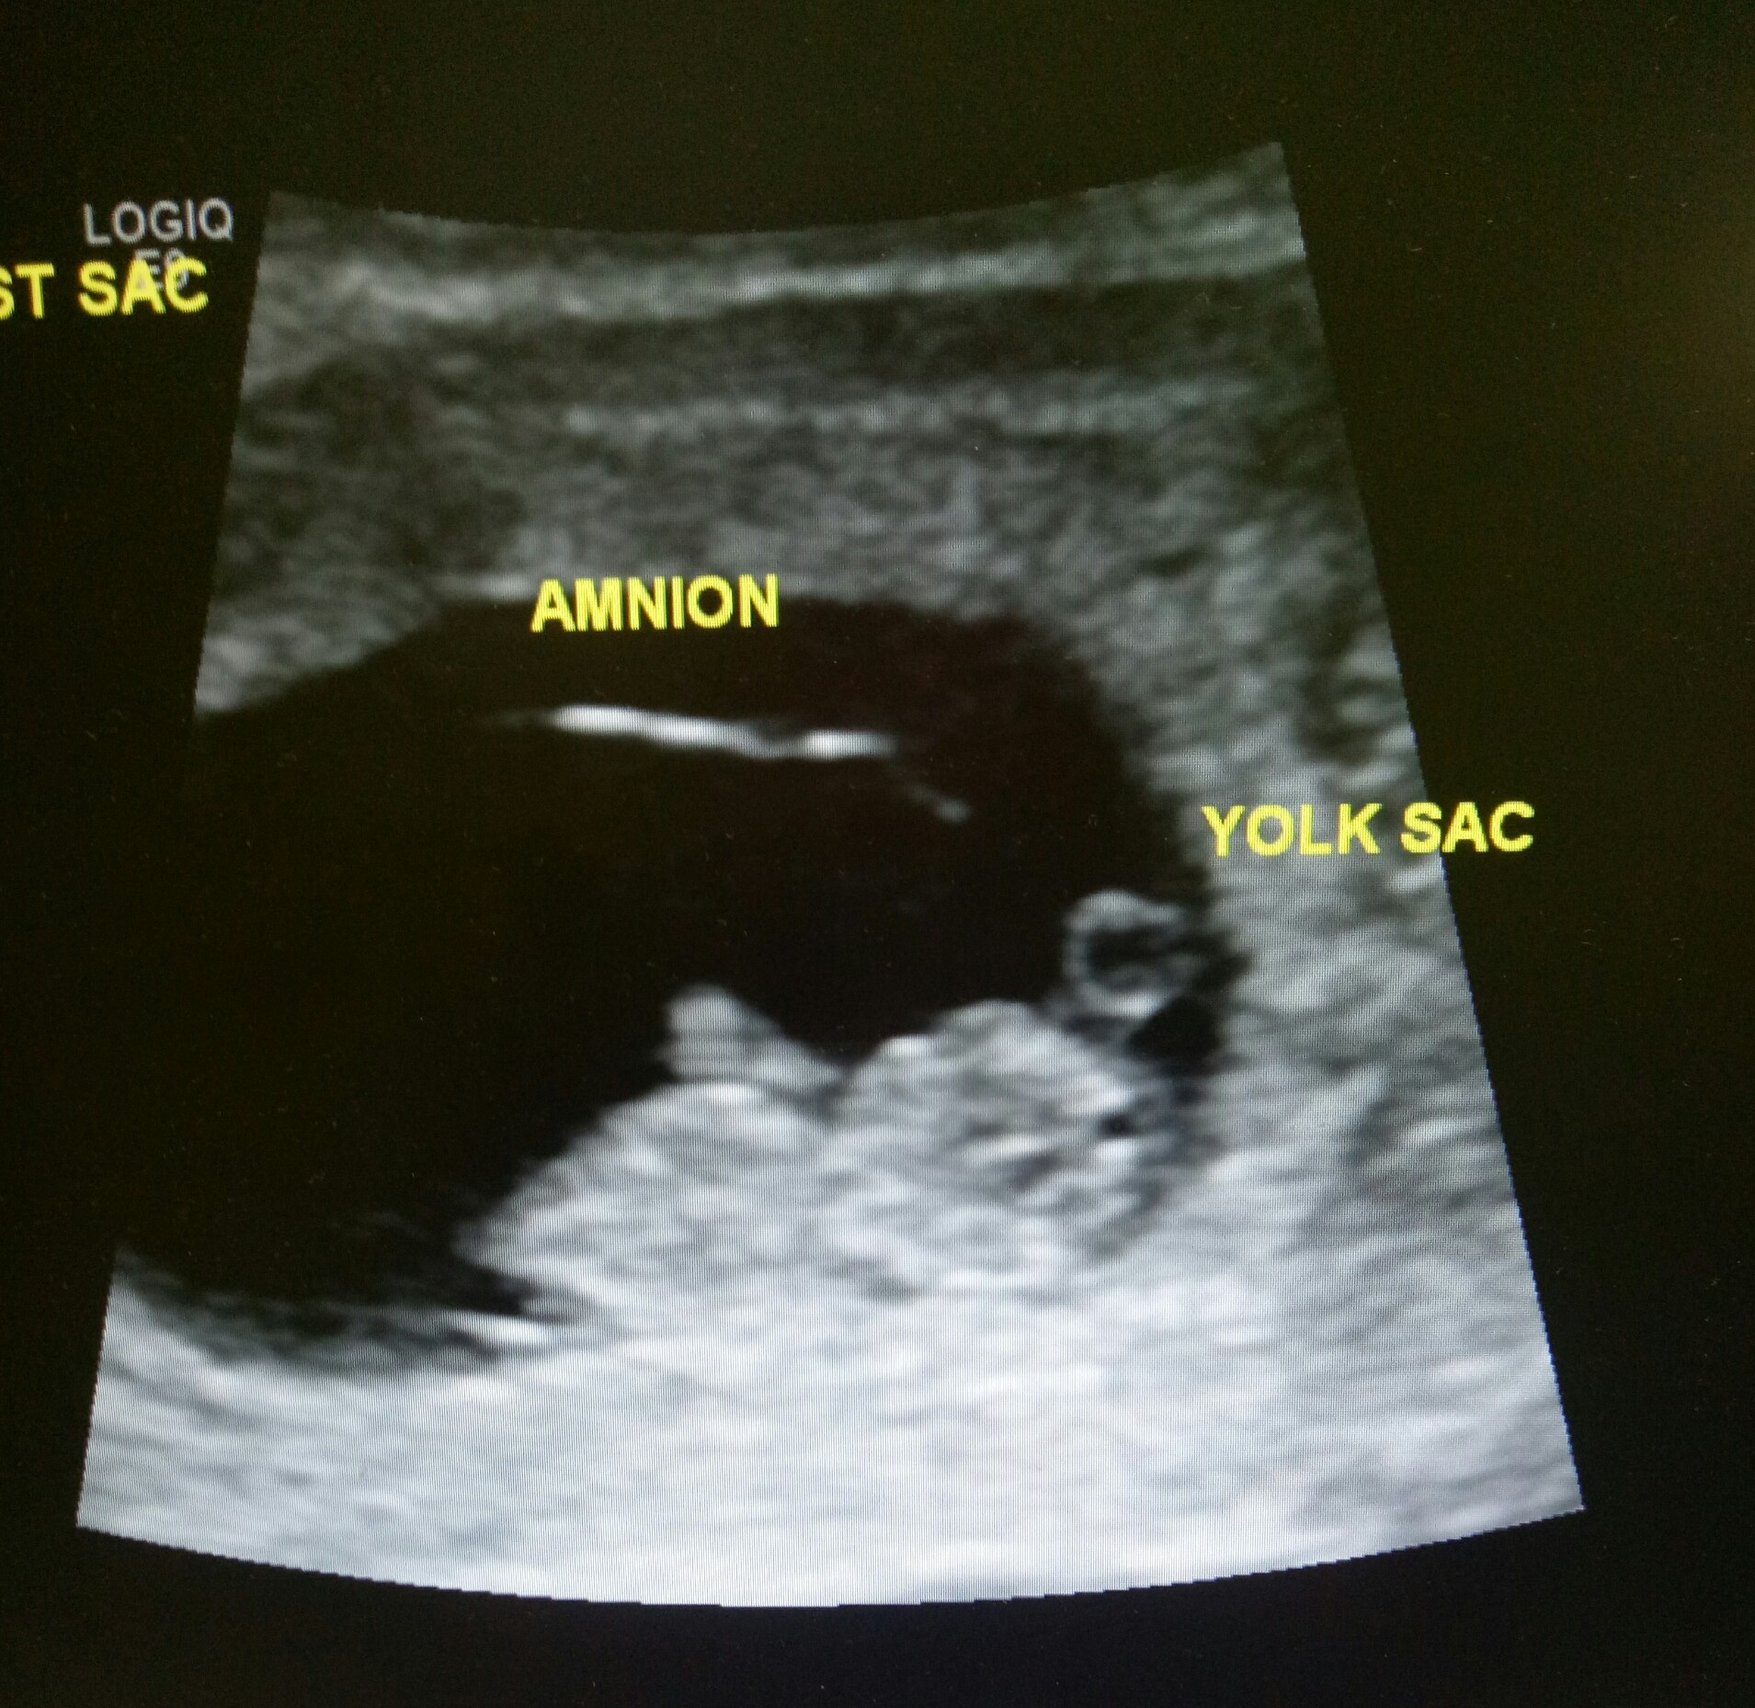

Had this ultrasound on Tuesday at 9w6d and was just wondering what you all think my little poppyseed will be, boy or girl. Healthy heart rate at 173bpm which I know leans towards girl however, looking for some opinions based on the ultrasound

By ramzi it looks like a girl, but ramzi also said I was havong 4 girls so take that with a grain of salt.